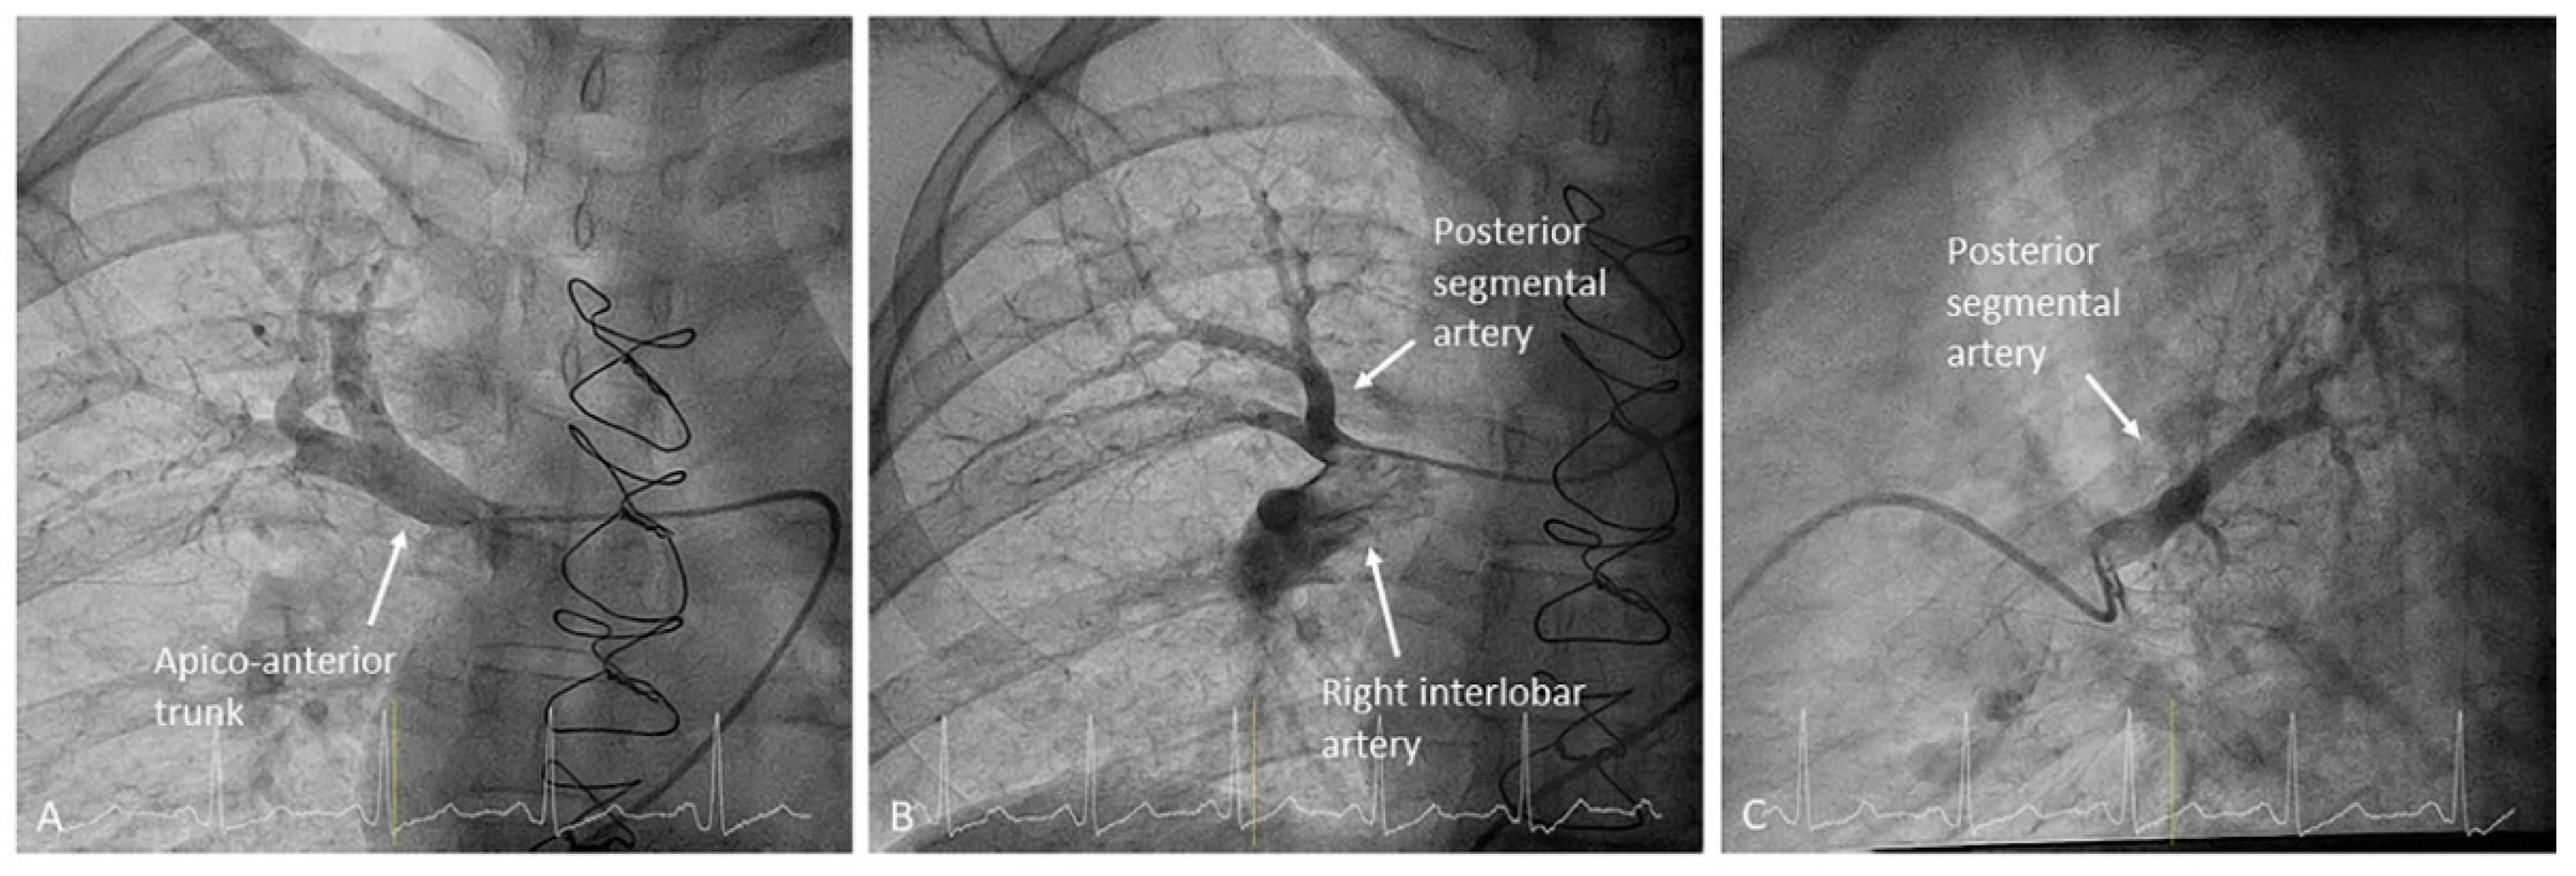

- Left upper lobe. The apico-posterior trunk (A1/2) is easily cannulated in the AP view. We should rotate the MP-A2 catheter counterclockwise in the proximal segment of the LPA to make the tip face upwards (Figure 23). The apical and posterior segmental arteries (A1 and A2) are well visualized by filming in the AP and lateral views. The anterior segmental artery (A3) is engaged more easily with the Judkins left catheter (JL) 3.5 or 4. Position the JL below the aortic arc in the AP view with the distal tip facing the left lateral chest wall. Rotate the catheter counterclockwise and withdraw it slightly. The distal tip of the catheter will climb 2–3 cm, engaging the anterior segmental branch (A3) (Figure 24). Film this branch in the cranial RAO and lateral views.

- Right upper lobe. The right upper lobar artery arises about 10 cm from the bifurcation. It is cannulated in the AP view with the tip of the MP-A2 facing upwards. The apico-posterior segmental artery (A1/2) is canalized just by advancing the MP distally once in the right upper lobe artery. The AP and lateral views display the apical (A1) and posterior branches (A2) (Figure 28). The anterior segmental artery (A3) is canalized in the lateral view, rotating the MP counterclockwise from its position in the apico-posterior artery (A1/2). With this maneuver, the tip of the catheter moves downwards, facing the sternum and engaging the anterior segmental artery (A3) (Figure 29). This branch should be filmed in lateral and cranial AP/cranial LAO view.